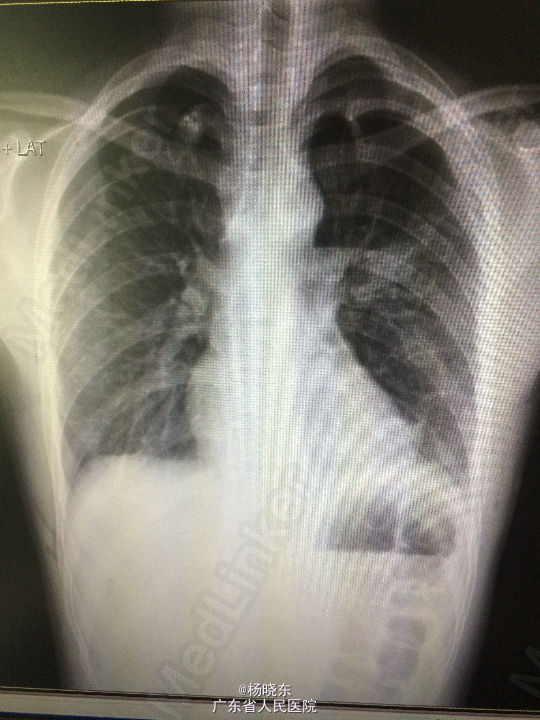

主诉:间断性胸闷、胸痛3年余,再发10余天。 病史:患者于3年余前出现左侧胸闷、胸痛。于当地医院就诊,诊断为左侧气胸(肺压缩10%),予对症处理(具体不详),1年余前再次出现左侧胸痛,于当地医院对症处理后好转,10余天前再次出现左侧胸痛,呈隐痛,无放射性牵涉痛,可忍受。自起病以来,精神睡眠胃纳可,大小便正常,体重无明显变化。

查体:心肺腹查体无特殊。 辅查:胸片

诊断:气胸 处理:完善相关检查后行胸腔镜双侧胸膜固定术,肺大疱切除术